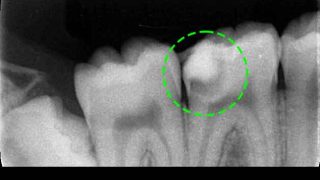

エルビウムヤグレーザー(Er:YAG)とMTAセメントを使用した間接覆髄の症例

↑上の画像を2回タップすると動画が再生されます 痛みは無くても虫歯が大きく、虫歯を除去して ...